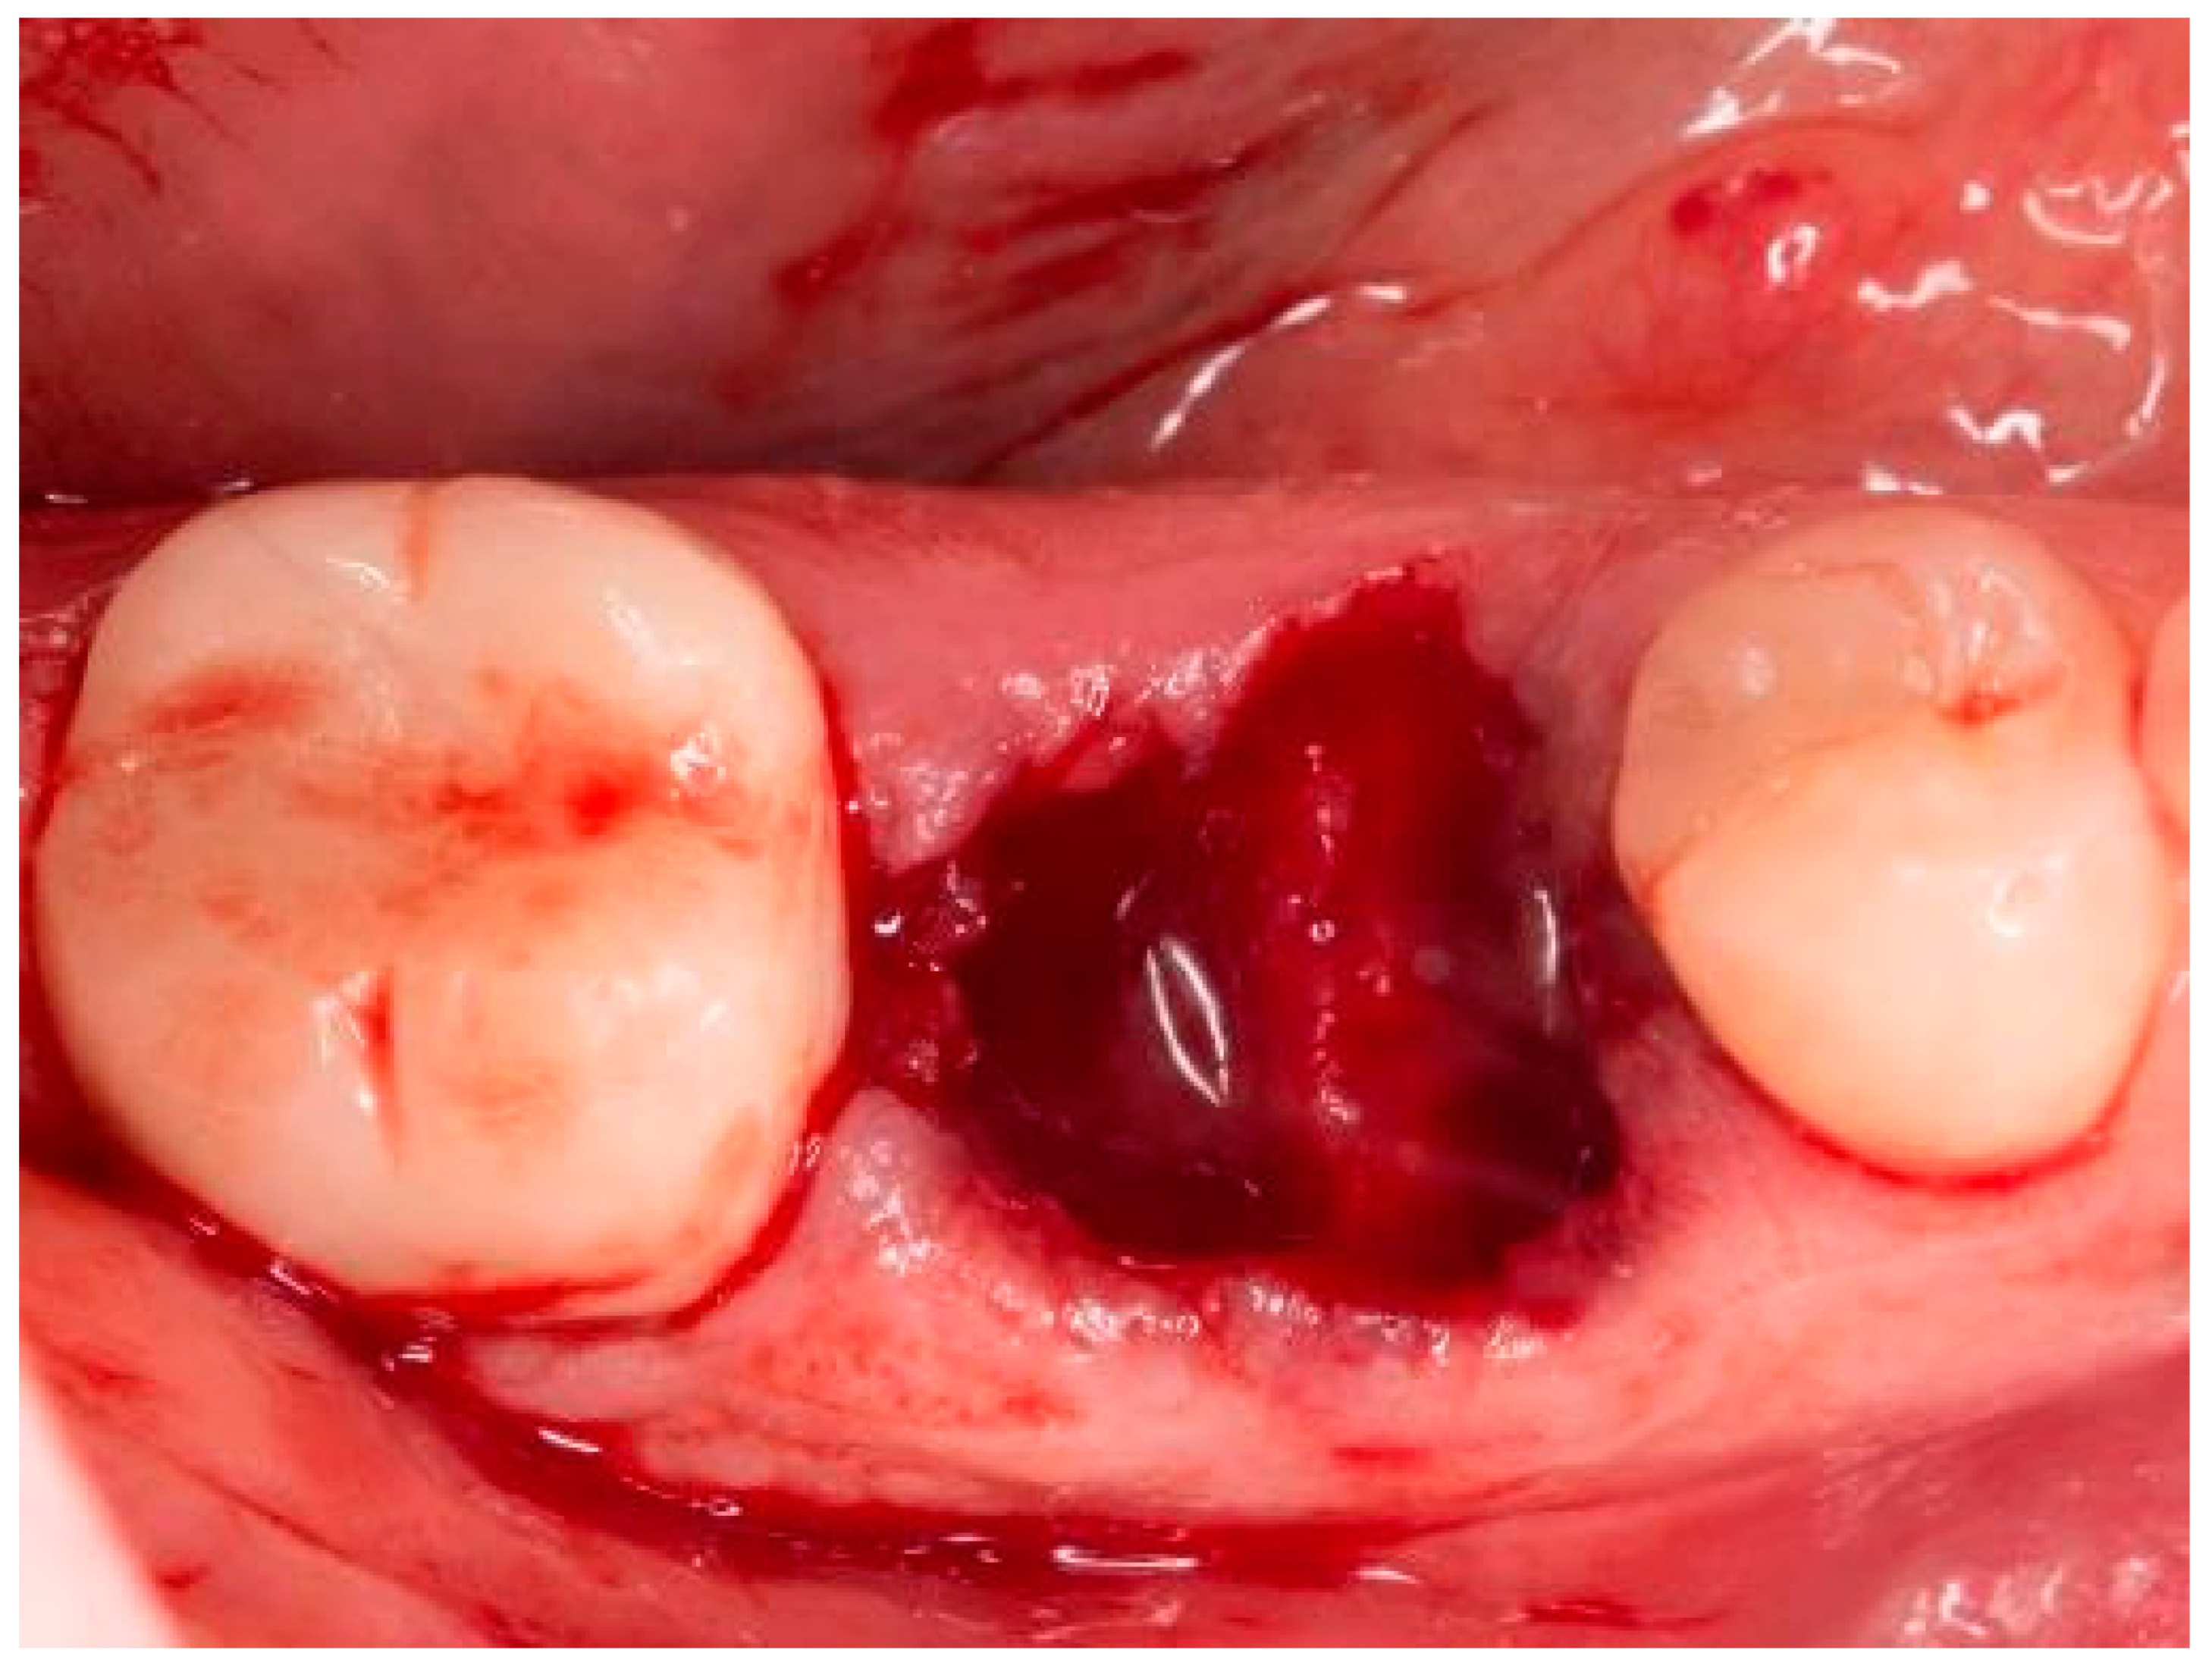

2. Materials and Methods